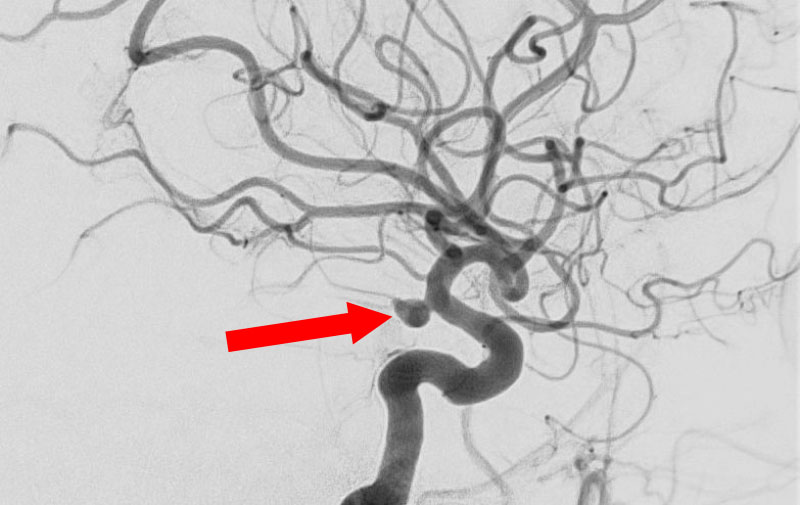

'25年10月

くも膜下出血

前交通動脈瘤破裂

40代

大阪府の病院

No.1589 手術前

No.1589 手術中

No.1589 手術後